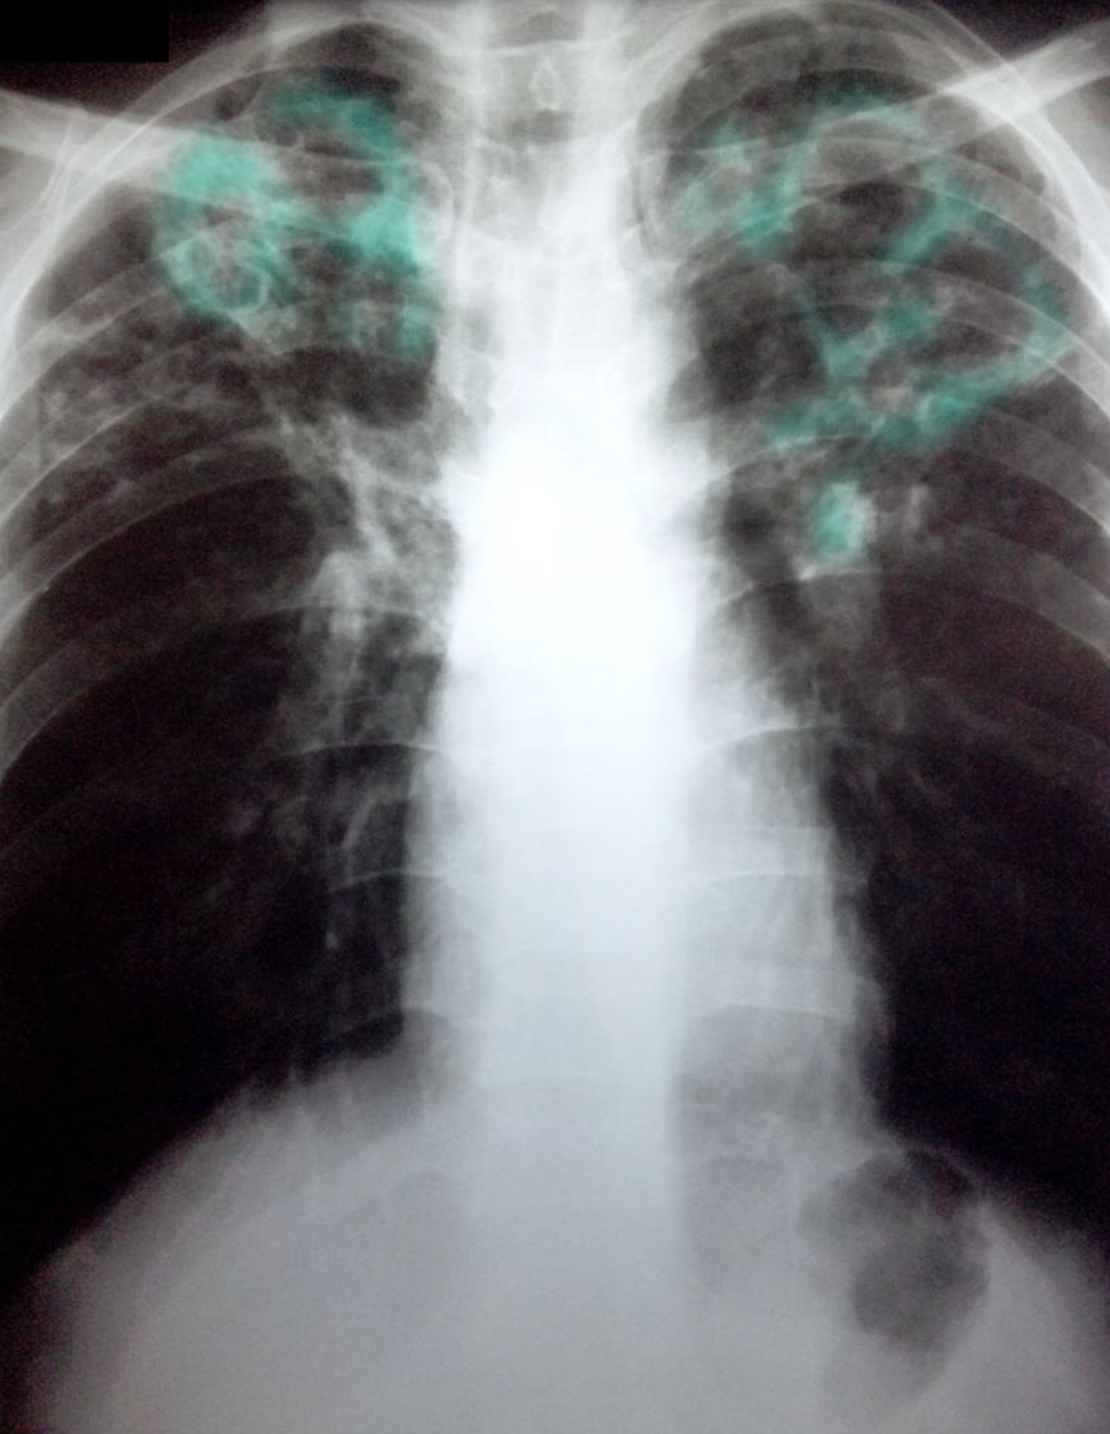

Post-primary tuberculosis

Posteroanterior chest x-ray showing bilateral apical, streaky parenchymal densities (green borders). These are most likely cavernous changes, which may occur during the course of post-primary tuberculosis. The full extent of cavernous formation can not be assessed on an x-ray; a CT scan should be performed.